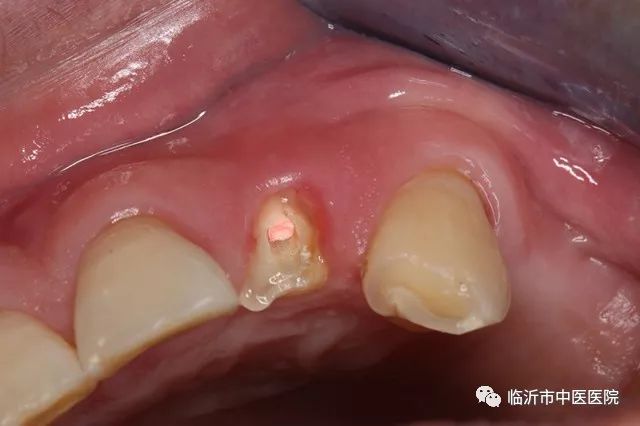

王振主任强调,遇到门牙牙冠于牙龈部位折断时,断冠完整无裂纹,根部稳无折断,可行接冠术。首先对断面进行清理,然后常规进行根管治疗,充填应密合。如断面在牙龈下,先将覆盖的牙龈组织切除,充分暴露断面。上述治疗完成后,再行接冠。选用成品或自制铸造桩钉,插入制备后的根管内,将断端调磨试接,直至复位,再取下备用。将桩钉粘固于根管内,断面进行粘接术前常规处理后于断面涂粘接剂及树脂材料,把断冠按位置复位,去除多余材料,光照固化。粘接完成后,适当调改咬颌,减轻患牙颌力。